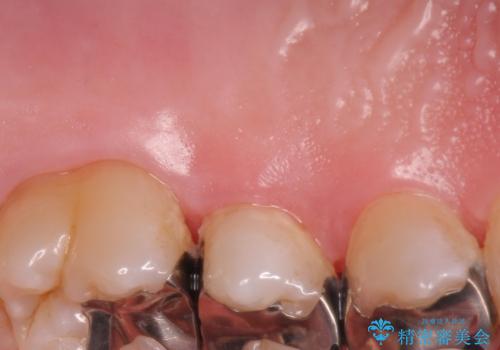

- 奥歯の歯茎が下がっていて(歯肉退縮)歯が染みるとのことで来院された患者様です。

歯根の分岐部よりも根尖側の頬側面が露出している状態でしたが、露出部位を分岐部までに抑えることができました。